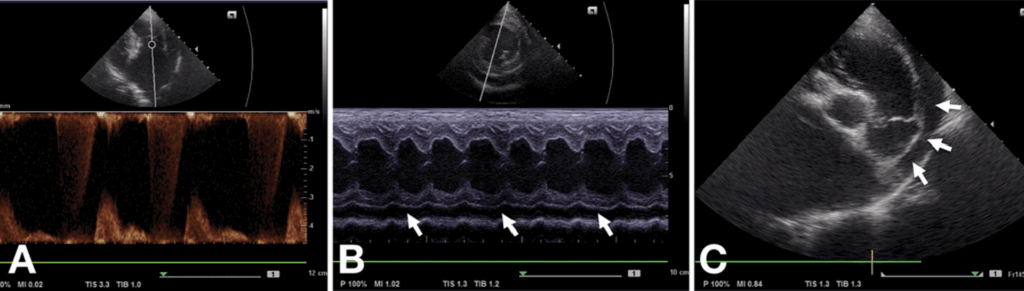

심낭수의 확인을 위해 심장초음파 검사가 진행되었습니다.

환자의 상태는 아래와 같이 파악되었습니다.

- 이첨판막의 심한 역류

- 심장의 왼쪽 방(좌심방)의 심한 확장

- 심장을 압박할 정도로 고인 심낭수

Fig 2. 환자의 초기 심장초음파 검사 영상입니다.

A: 좌측 흉골 옆 단면에서 심실 수축기 동안 심실에서 심방으로 3.5 m/s 이상의 승모판 역류가 관찰됩니다.

B: 우측 흉골 옆 유두근(papillary muscle) 수준의 M-mode 영상에서 좌심실 자유벽 아래쪽에 심낭수(흰색 화살표)가 보입니다.

C: 폐동맥 수준의 우측 흉골 옆 단면에서 폐동맥 줄기 우측 위쪽에 심낭수(흰색 화살표)가 보이며, 좌심방/대동맥 비율이 2.0 이상으로 좌심방이 크게 확장되어 있습니다.

( Initial echocardiography of the patient.

A: In the left parasternal view, mitral regurgitation > 3.5 m/s is observed from the ventricle to the atrium during ventricular systole.

B: The M-mode image at the papillary muscle level in the right parasternal view shows pericardial effusion (white arrows) under the free wall of the left ventricle.

C: The right parasternal view at the pulmonary artery level shows pericardial effusion (white arrows) over the right side of the pulmonary trunk and an enlarged left atrium (left atrial/aortic root ratio > 2.0).)